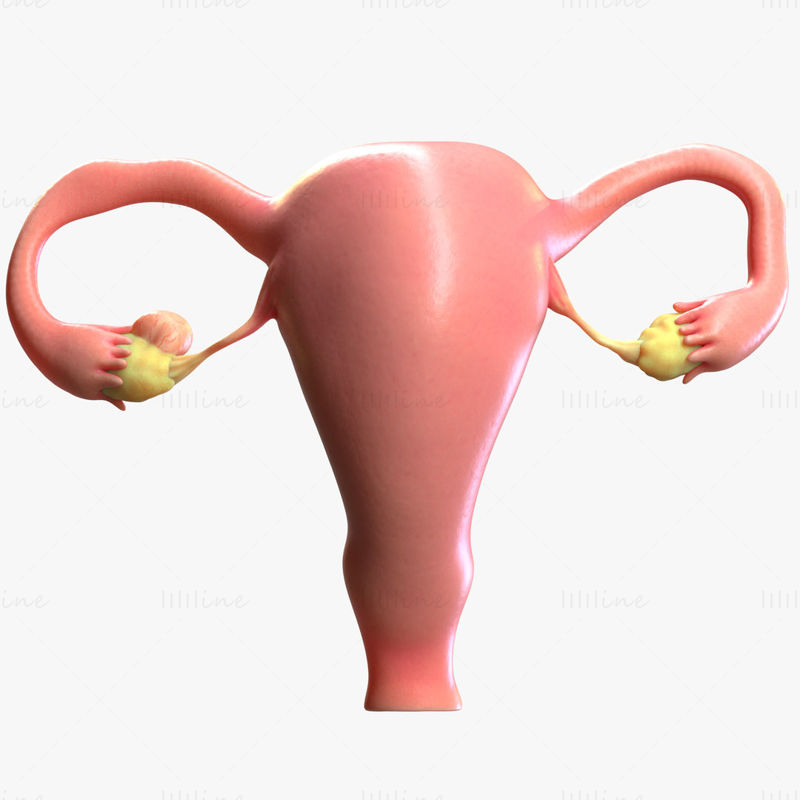

Анатомия женского организма: строение и функции матки

Раздел: Фотопуть к знанию